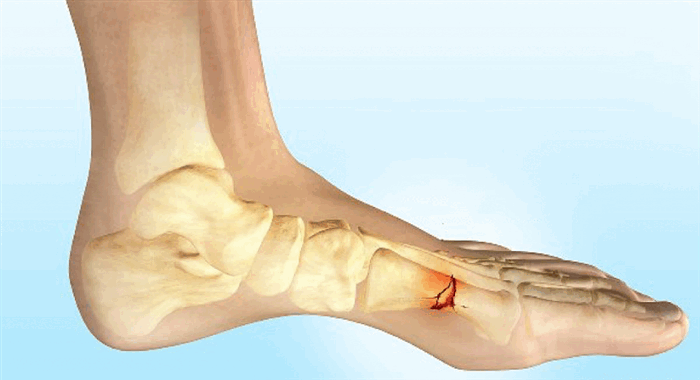

По данным хирургов-ортопедов, сильнее других костей стресс-перелому подвержены вторая и третья плюсневые косточки стопы. Область, где они располагаются, сильнее всего задействована в беге. Она отвечает за отталкивание.

Стрессовые переломы могут охватить и пятку, и лодыжку, и среднюю часть стопы, и даже таз, крестец: в общем, все те области, которые подвергаются ударам, а мышцы вследствие усталости не могут их поглощать. Но у бегунов чаще всего страдают кости голени или стопы, ведь именно они самые рабочие для этого вида спорта. Речь идет о несущих костях – берцовой и плюсневых.

Стрессовые переломы происходят в костях, претерпевающих механическую усталость. Они являются следствием чрезмерных повторяющихся субмаксимальных нагрузок, которые создают дисбаланс между костной ресорбцией и формированием. Переломы обычно возникают в месте наибольшей нагрузки; это называют «образованием трещин». Если эту микроскопическую трещину невозможно вылечить и подвергать ее дальнейшим нагрузкам, микроповреждение увеличится, и трещина увеличивается в размерах. Такое увеличение может быть причиной перелома кости на макроскопическом уровне.